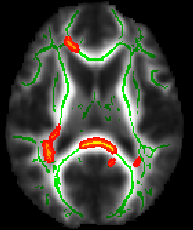

You will probably next want to load the mean_FA_skeleton image on top of your background image, to show where the skeleton was estimated, and which standard-space voxels were tested in the multi-subjects statistics. Load mean_FA_skeleton into FSLView and set its display range correctly. The lower threshold must be set to the threshold that you used in the TBSS analysis, for example 0.2. The upper level should probably be set to something like 0.7, so that you can see variation in mean FA values within the skeleton. You probably want to change the colourmap, for example to Green, and increase the transparency (with the transparency slider) so that when you load the stats image in, it is easier to see.

Finally, load the stats image in. If you have used TFCE-based testing in randomise, the raw t-statistic image will be named something like tbss_tstat1 (which you could view to see raw tstats before significance testing), but the image you probably want is tbss_tfce_corrp_tstat1, which is the corrected p-value image (actually the values in this image are 1-p for ease of display, so that bigger is "better"). Load this into FSLView, set a colourmap such as Red-Yellow, and set the display range to something like 0.95:1, which corresponds to thresholding the results at p<0.05.

All of the above (apart from setting the skeleton transparency, which has to be done by hand in the GUI) can be carried out with a single command (see first example image):

fslview $FSLDIR/data/standard/MNI152_T1_1mm mean_FA_skeleton -l Green -b 0.2,0.7 tbss_tfce_corrp_tstat1 -l Red-Yellow -b 0.95,1